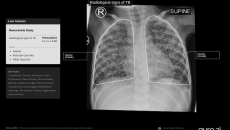

CE mark for India-made AI for screening TB in toddlers

Its chest X-ray analysis AI tool is the first to receive Europe's clearance for use in children aged 0-3.